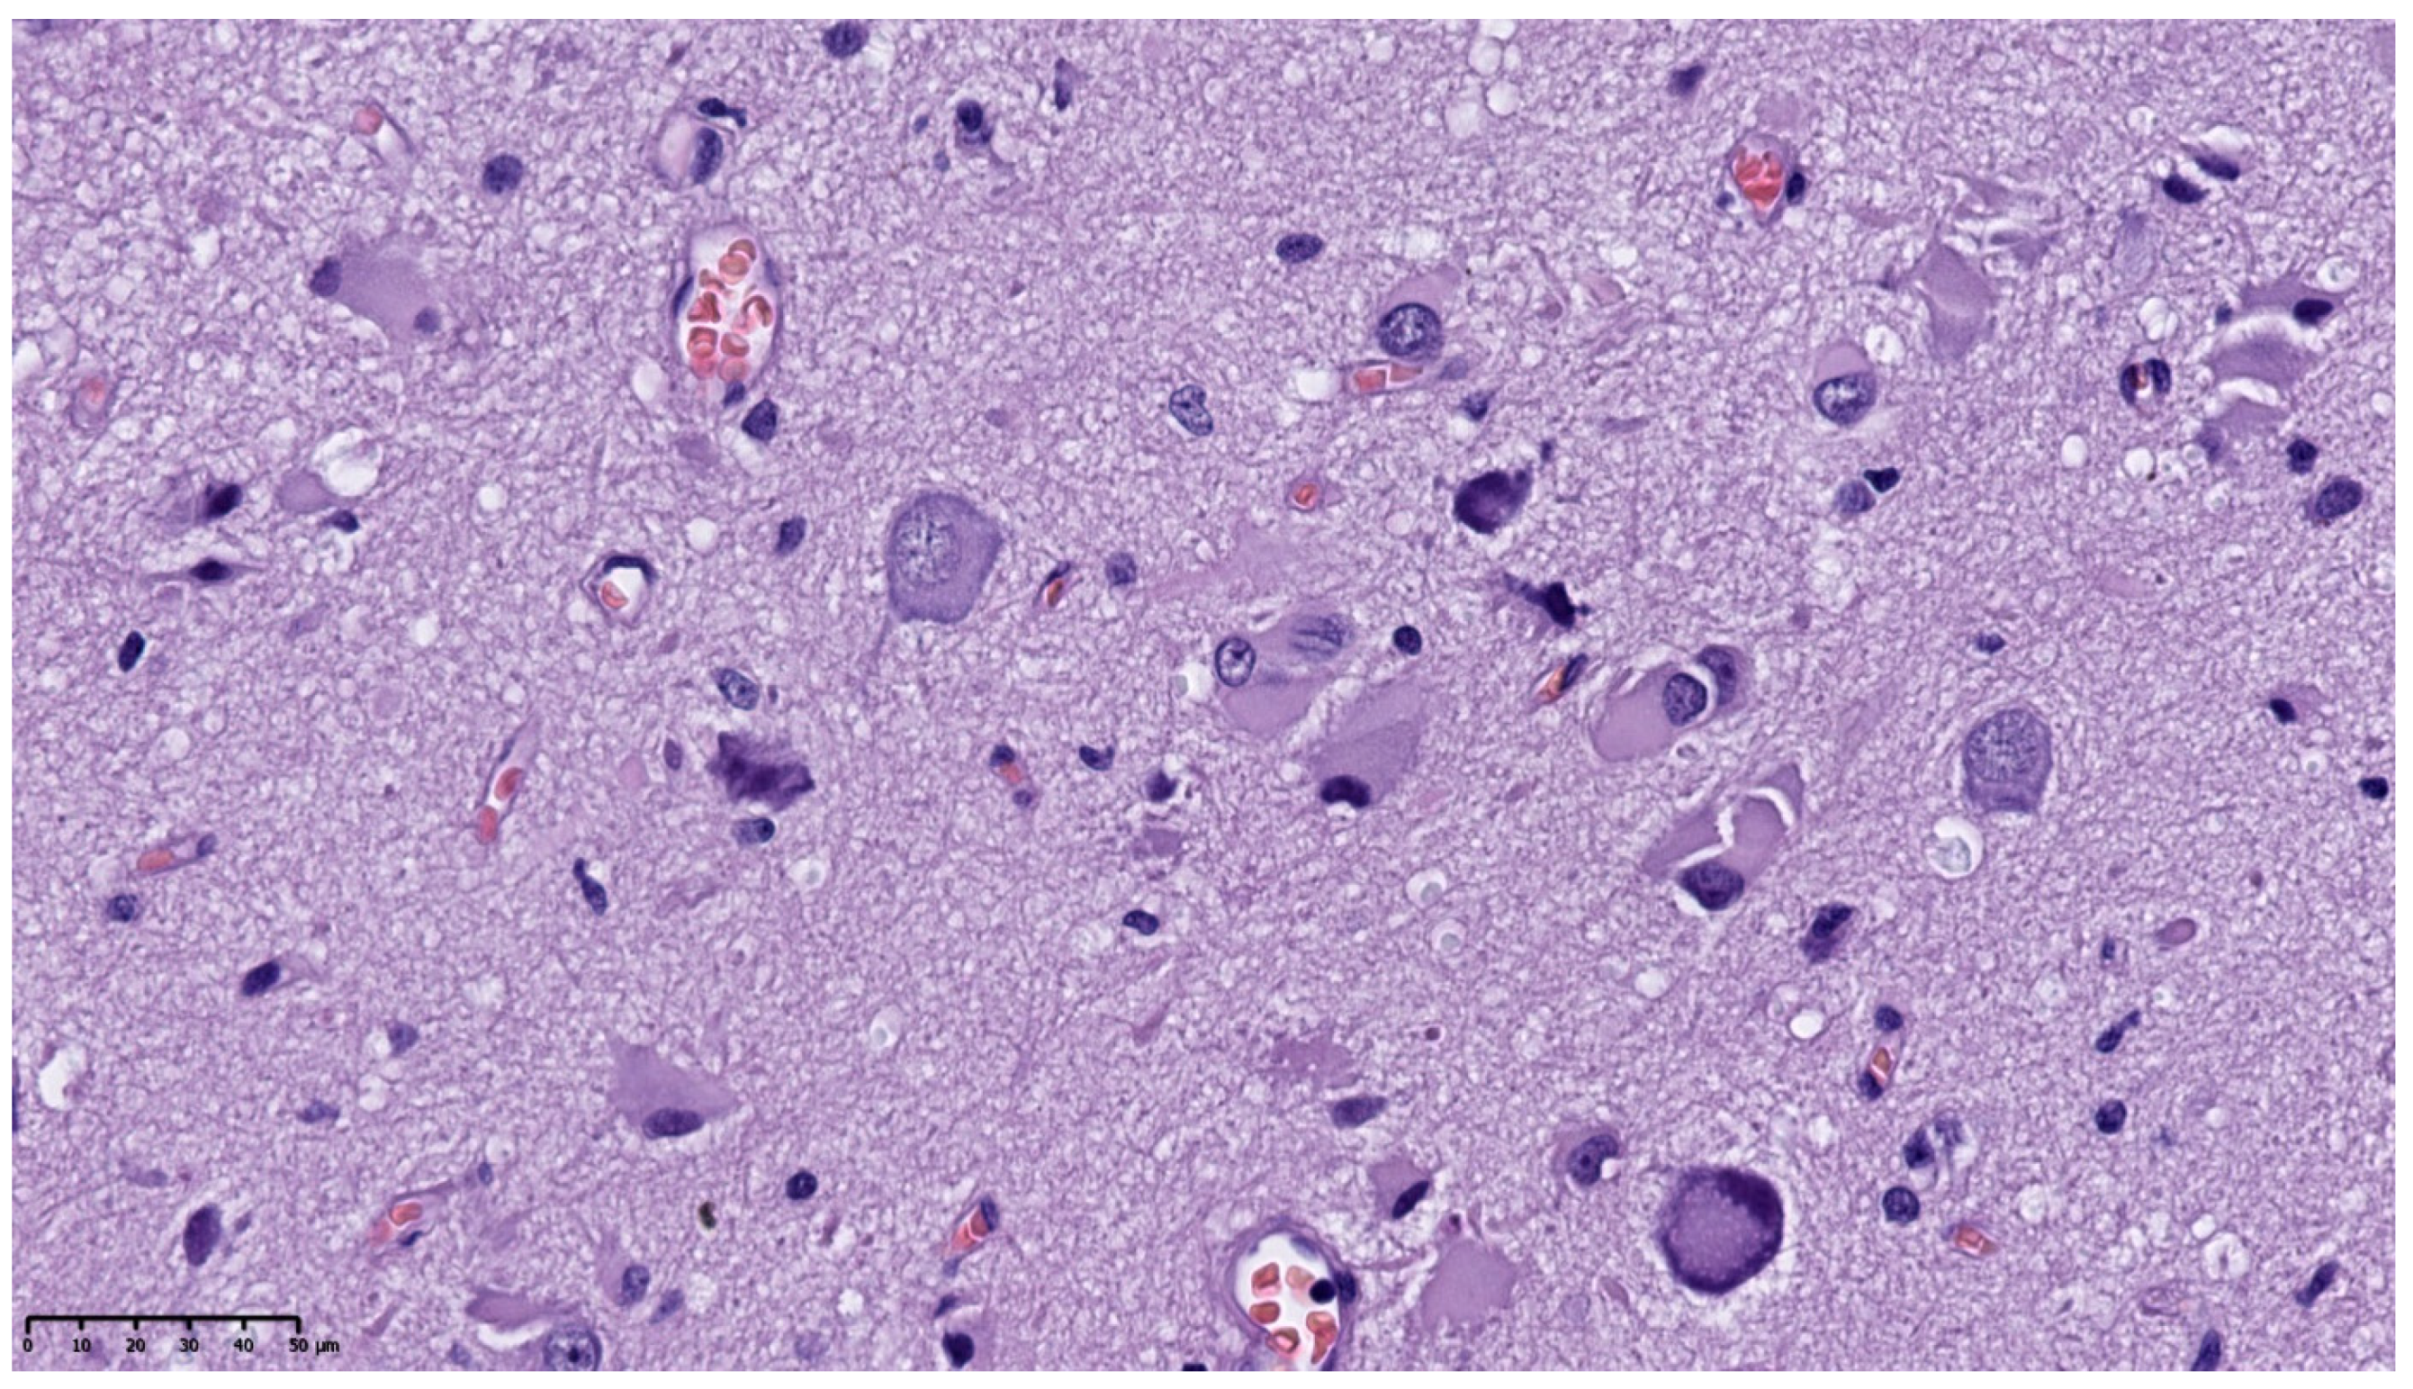

3.1. Clinical and Pathology Report